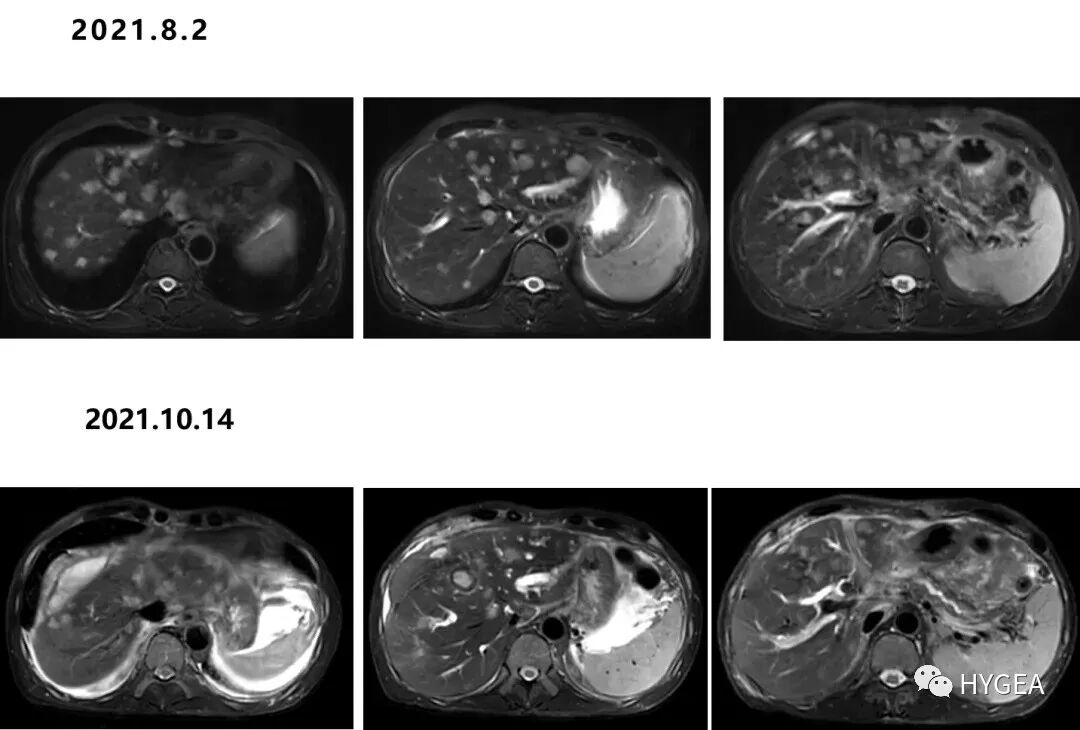

▲黄先生术后复查MRI见:病灶明显缩小、减少,疗效判断为PR